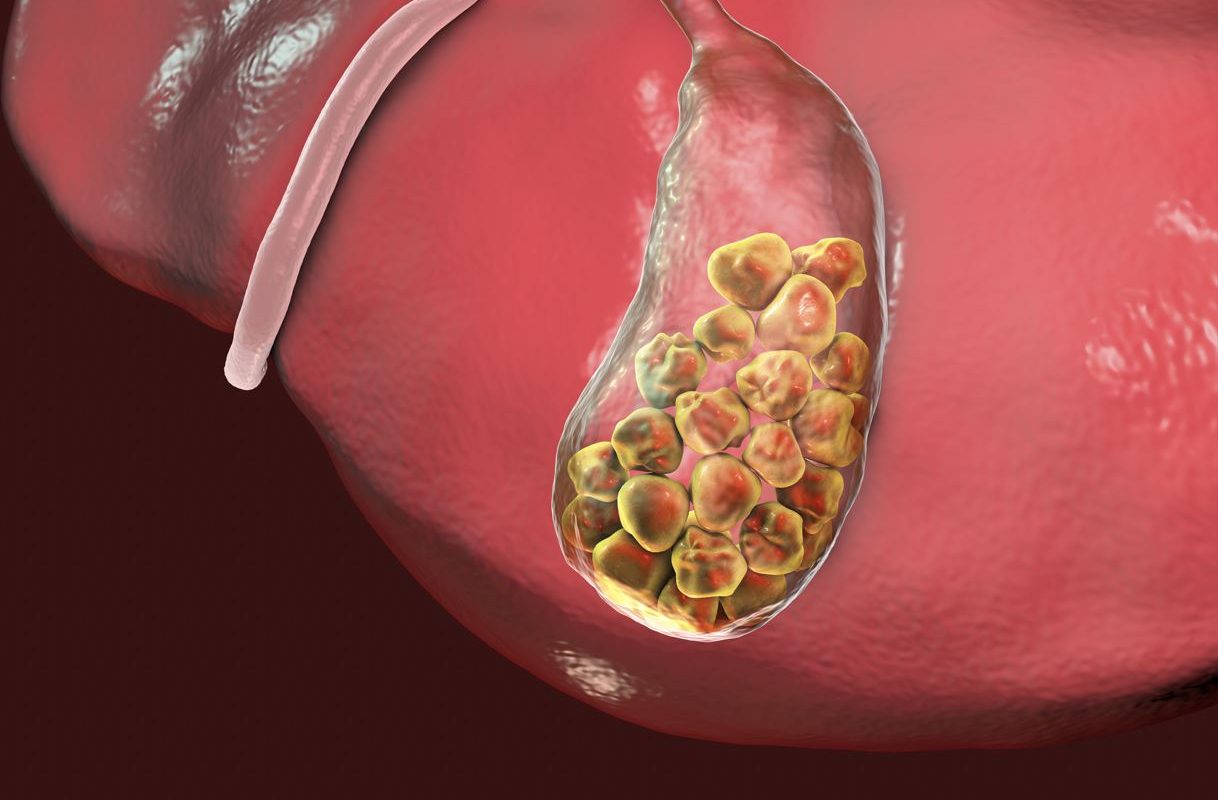

There is a little organ called the gallbladderin your upper right belly, directly beneath your liver. Bile, a greenish-yellow liquid that aids in digestion, is kept in this pouch. Sometimes, gallstones obstruct the bile duct. Most gallstones are caused by the hardening of bile-derived chemicals like cholesterol. Gallstones are often asymptomatic and quite prevalent. However, only 10% of those with gallstones will have symptoms within 5 years.

Yellow cholesterol stones might develop if your bile contains an excessive amount of cholesterol. If your liver produces more cholesterol than your bile can break down, these hard stones may form.

A substance called bilirubin is created as part of the regular breakdown of red blood cells. Following production, it moves through the liver before being removed from the body.Your liver may overproduce bilirubin under certain circumstances, such as liver disease and some blood diseases. When your gallbladder is unable to break down the extra bilirubin, pigment gallstones develop. They are typically black or dark brown.

Concentrated bile